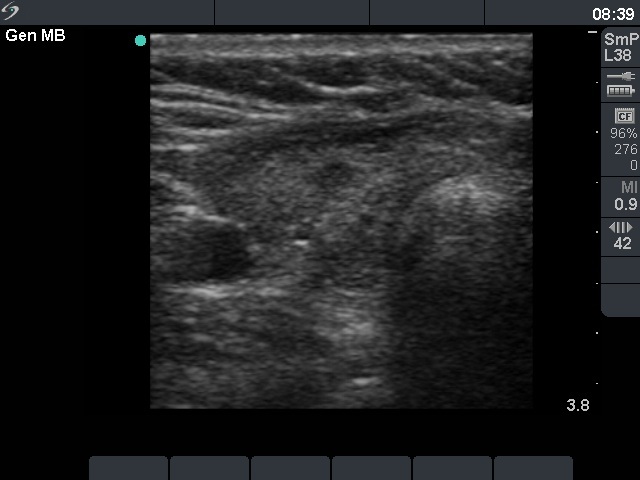

One year after surgery (third row of images)

Results of blood test: subclinical hyperthyroidism on daily 25 microgram levothyroxine (TSH 0.09 mIU/L, FT4 17.9 pM/L).

Ultrasonography: There was no parenchyma according to the right lobe, while there was a relatively large thyroid tissue in the left lobe. The latter displayed increased vascularization.

TSAb was undetectable. The replacement therapy has stopped. We offered regular follow-up.